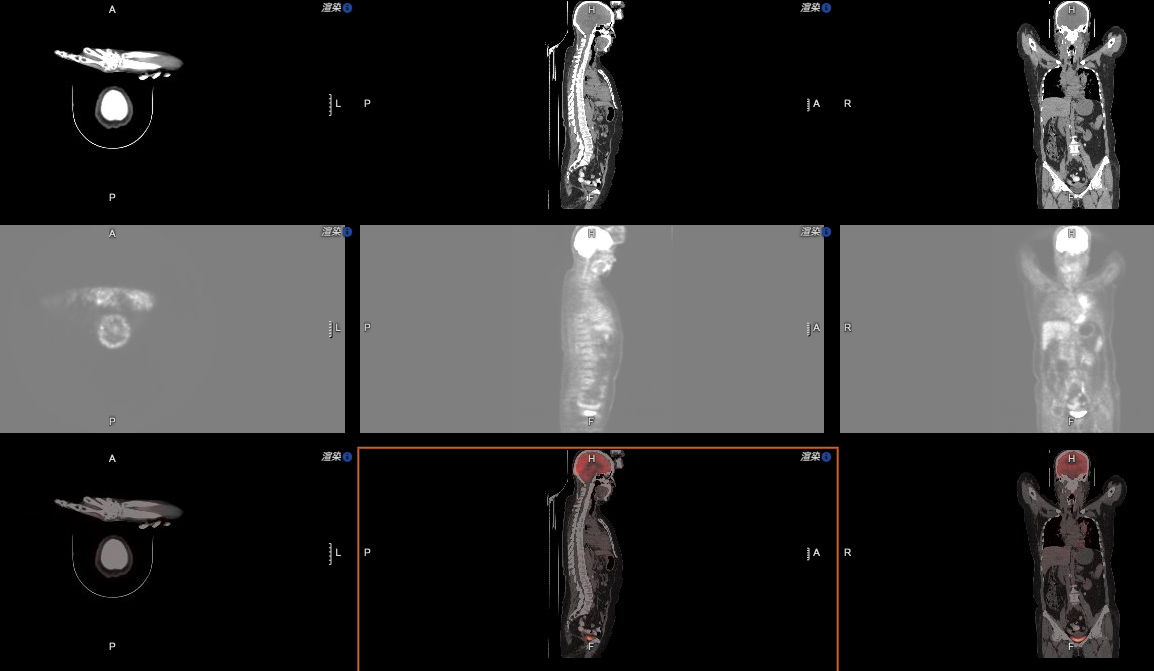

再看这张图:

相信对于具备PET/CT的医疗机构来说,这样的影像软件功能同样是必需的。